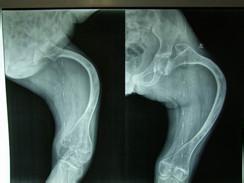

辅助检查X线表现检查。超声检查超声检查胎儿的骨骼系统可早期发现先天性骨发育障碍性疾病。Garjian等的经验显示,三维超声可得到立体解剖定位,故优于二维超声检查,前者更易发现头、面部和肋骨的畸形。

诊断/成骨不全 编辑主要有四项诊断标准,成骨不全图册骨质疏松和骨的脆性增加。蓝巩膜。牙质形成不全早熟性耳硬化上述4项中出现2项特别是前2项,即可诊断。结合影像学检查有助于诊断。 但有时要与严重的佝偻病相区别。另外也应与软骨发育不全,先天性肌弛缓,甲状腺功能减退及甲旁亢等区别。对于婴儿和儿童的轻度成骨不全症的临床诊断也许会比较困难,需要具有治疗所有类型成骨不全症的临床经验的遗传学家、整形外科医生或内分泌学家来进行治疗。实验室研究可以排除其他因素,提供对疗法有用的信息,并且在多数情况下能够通过突变鉴定来确诊。